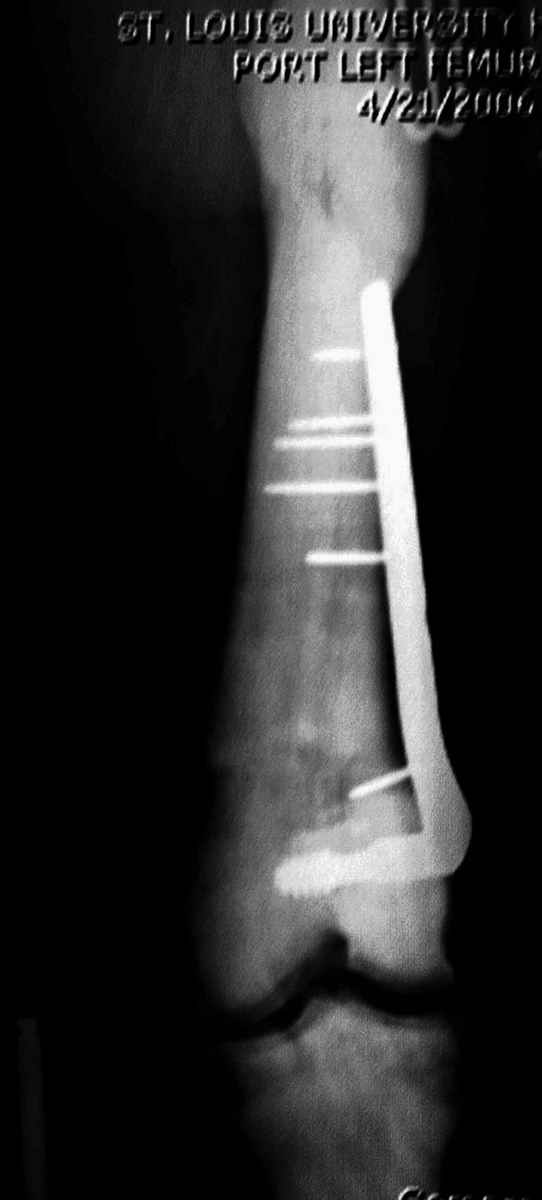

После неудачной попытки скелетного вытяжения в первом мед.учреждении, после осмотра снимков и изучения истории, поставили диагноз “Остеопетроз” или мраморная болезнь, редкая наследственная костная паталогия, где имеется нарушение формации остеокластов.

Конечно, было бы идеальным применение интрамедуллярного остеосинтеза, но учитывая прежний собственный опыт (лечил перелом бедра) и

публикации, предупреждающие о трудностях при обработке кости (иногда из-за неподготовленности инструментария результатом была неадекватная фиксация перелома, или перенос операции из-за фактора усталости оперирующего персонала), решили применить пластину (и в этом же случае был выбран Synthes plate, так что представитель за два дня

зароботал... на десерт тоже).

Заказаны были дополнительные различные дрели, и на следующий день, усиленной бригадой, больного прооперировали, потратив на каждое отверстие около 25-35 минут, хотя сверлили с охлаждением по нарастающей по диаметру сверл и с их заменой каждые 2 мм сверления.

Теперь стоит задача со сращением перелома, из-за отсутствия литературных данных по применению костных стимуляторов при остеопетрозе, и не зная как поведет в этой среде Grafton, все таки надеюсь, что даст толчок к стимуляцию, решил применить пастообразную деминерализованную костную матрицу, расположив спереди между отломками.